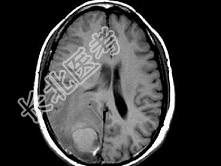

- 单项选择题女,46岁, 头痛、头昏半月入院,根据所提供图像, 最可能的诊断是 ( )

A、转移性乳头状腺癌

B、胶质瘤

C、脑脓肿

D、胶质母细胞瘤

E、毛细胞型星形细胞瘤